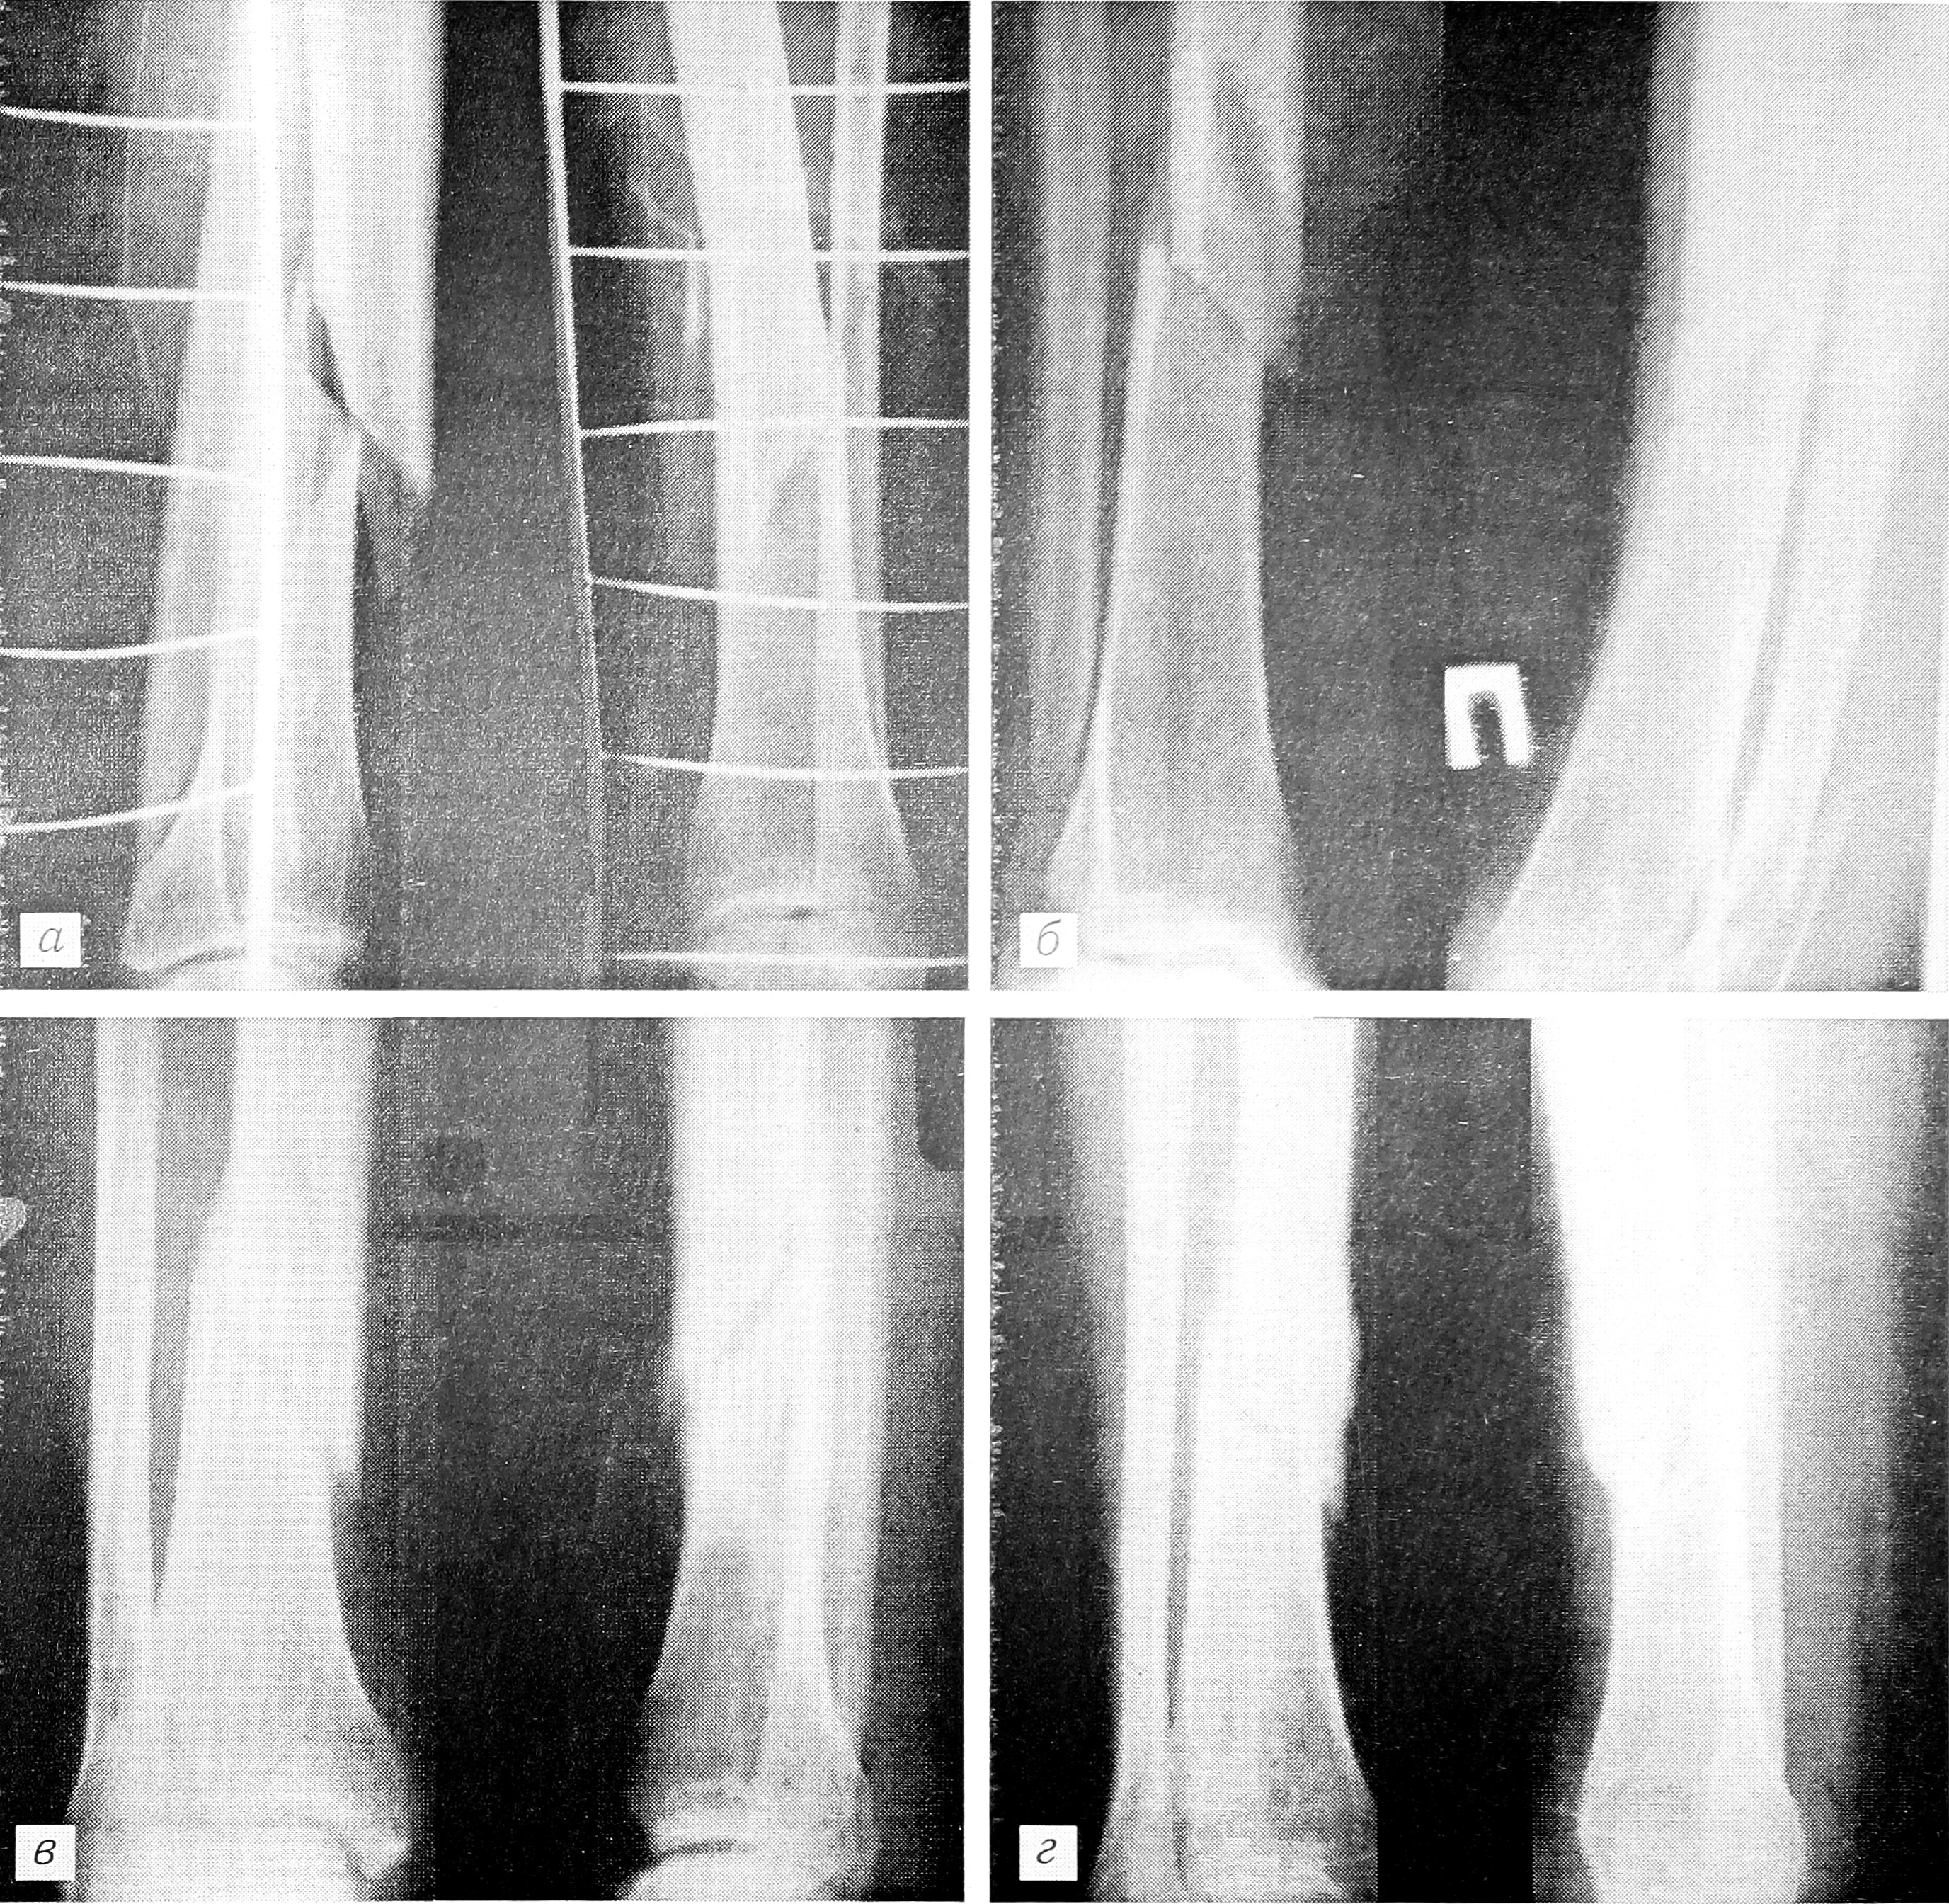

Сравнительный анализ рентгенограмм больных основной и контрольной групп показал более раннее (на 7—10 дней) появление признаков первичной мозоли после воздействия СМП (рис. 1 и 2 на вклейке). В контрольной группе у 5% больных отмечено несращение костей голени. Эти пациенты впоследствии были оперированы.

Рис. 1. Рентгенограммы больного с закрытым винтообразным переломом костей правой голени, леченным без применения сканирующего магнитного поля.

а — при поступлении; б — на 5-е сутки (скелетное вытяжение); в — через 3 мес (снята гипсовая повязка) г — через 5 мес: костная мозоль слабая.